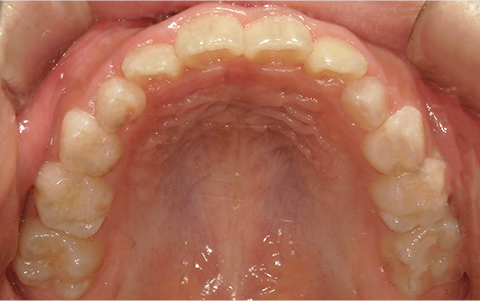

症例